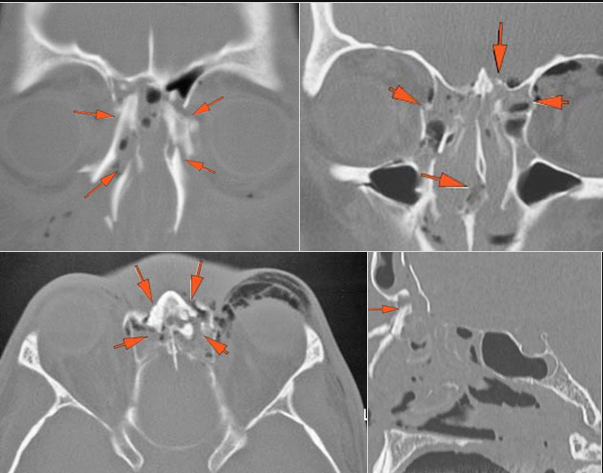

Right Temporal Bone

The external auditory canal shows abnormal soft tissue thickening.

The roof of the mastoid and/or middle ear is fractured.

A possible meningocele and/or encephalocele or CSF leak is present.

The ossicles, in particular the incus long process, the incudostapedial joint and stapes are fractured or dislocated.

The facial canal including the labyrinthine, tympanic and descending portions and nerve are fractured.

The inner ear including the lateral semicircular canals, vestibule and/or cochlea is fractured or otherwise abnormal.

There is subperiosteal, epidural or subdural hematoma along the roof of the mastoid or middle ear or the superior and posterior (intracranial) surfaces of the petrous portion of the temporal bone.

Left Temporal Bone